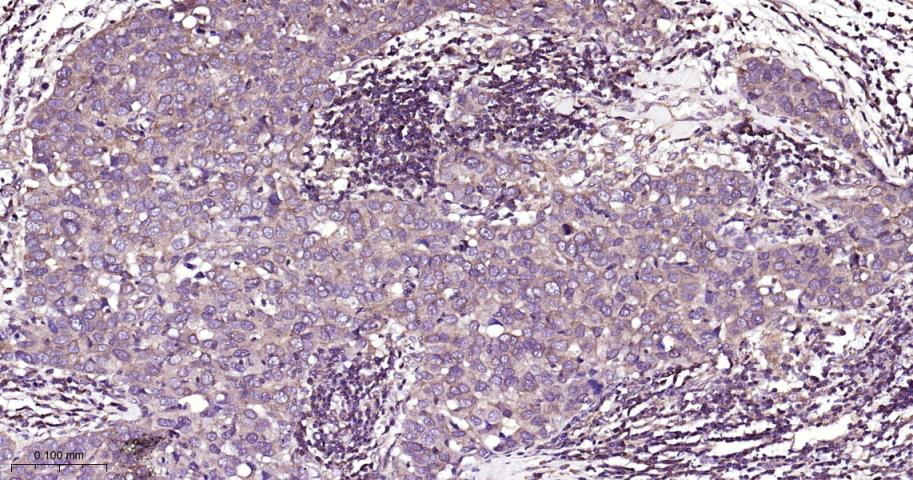

Paraformaldehyde-fixed, paraffin embedded Human Glioma; Antigen retrieval by boiling in sodium citrate buffer (pH6.0) for 15 min; Antibody incubation with PKC Monoclonal Antibody, Unconjugated(bsm-62952R) at 1:200 overnight at 4°C, followed by conjugation to the bs-0295G-HRP and DAB (C-0010) staining.

Paraformaldehyde-fixed, paraffin embedded Human Spleen; Antigen retrieval by boiling in sodium citrate buffer (pH6.0) for 15 min; Antibody incubation with PKC Monoclonal Antibody, Unconjugated(bsm-62952R) at 1:200 overnight at 4°C, followed by conjugation to the bs-0295G-HRP and DAB (C-0010) staining.